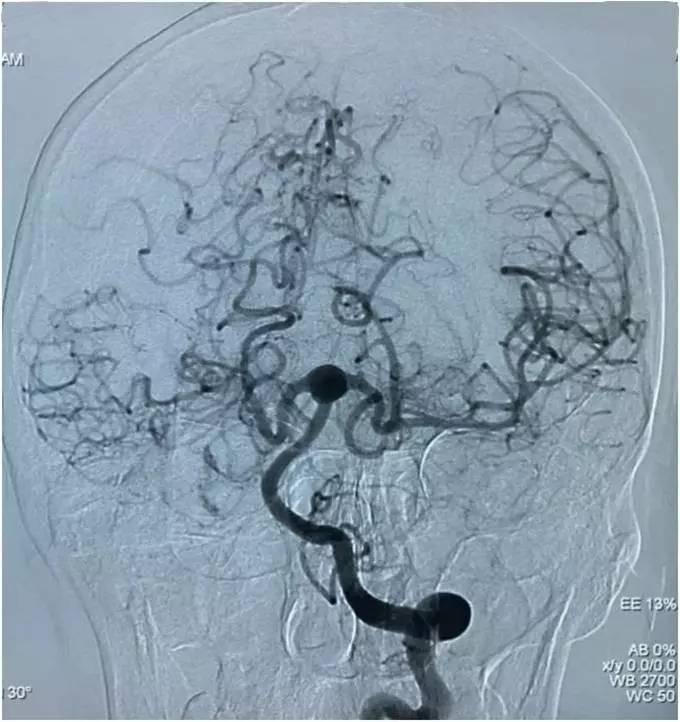

以下图像为DSA,显示基底动脉顶端动脉瘤,左侧小脑上动脉瘤,左侧PCA P1段微小动脉瘤,双侧颈内动脉眼动脉以远闭塞,前循环靠后循环通过后交通动脉代偿。

▼左椎动脉造影侧位

▼左椎动脉造影三维重建,这个角度可以窥清基底动脉顶端动脉瘤和左小脑上动脉瘤,可见基底动脉顶端动脉瘤顶端的子瘤,考虑是SAH的责任动脉瘤。